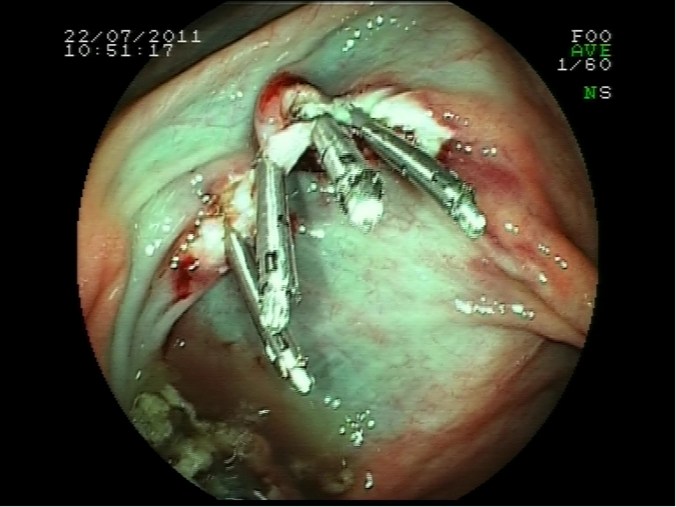

Escara post polipectomía, sutura con clips